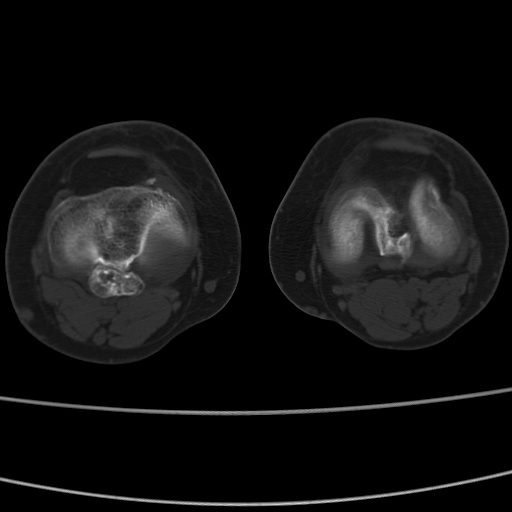

女性,50岁。【请提供患者临床症状体征】

右膝关节退行性改变,关节游离鼠。

右膝关节退行性改变,滑膜黏液囊钙/骨化并游离。

右膝关节退行性改变